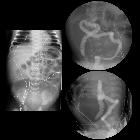

Newborn with

failure to pass meconium. AXR (left) shows multiple dilated loops of bowel with an extremely dilated loop of bowel in the lower abdomen. AP (above right) and lateral (below right) images from an enema show a microcolon with contrast reaching the level of the cecum but not refluxing the terminal ileum, despite multiple attempts. The diagnosis was colonic atresia.